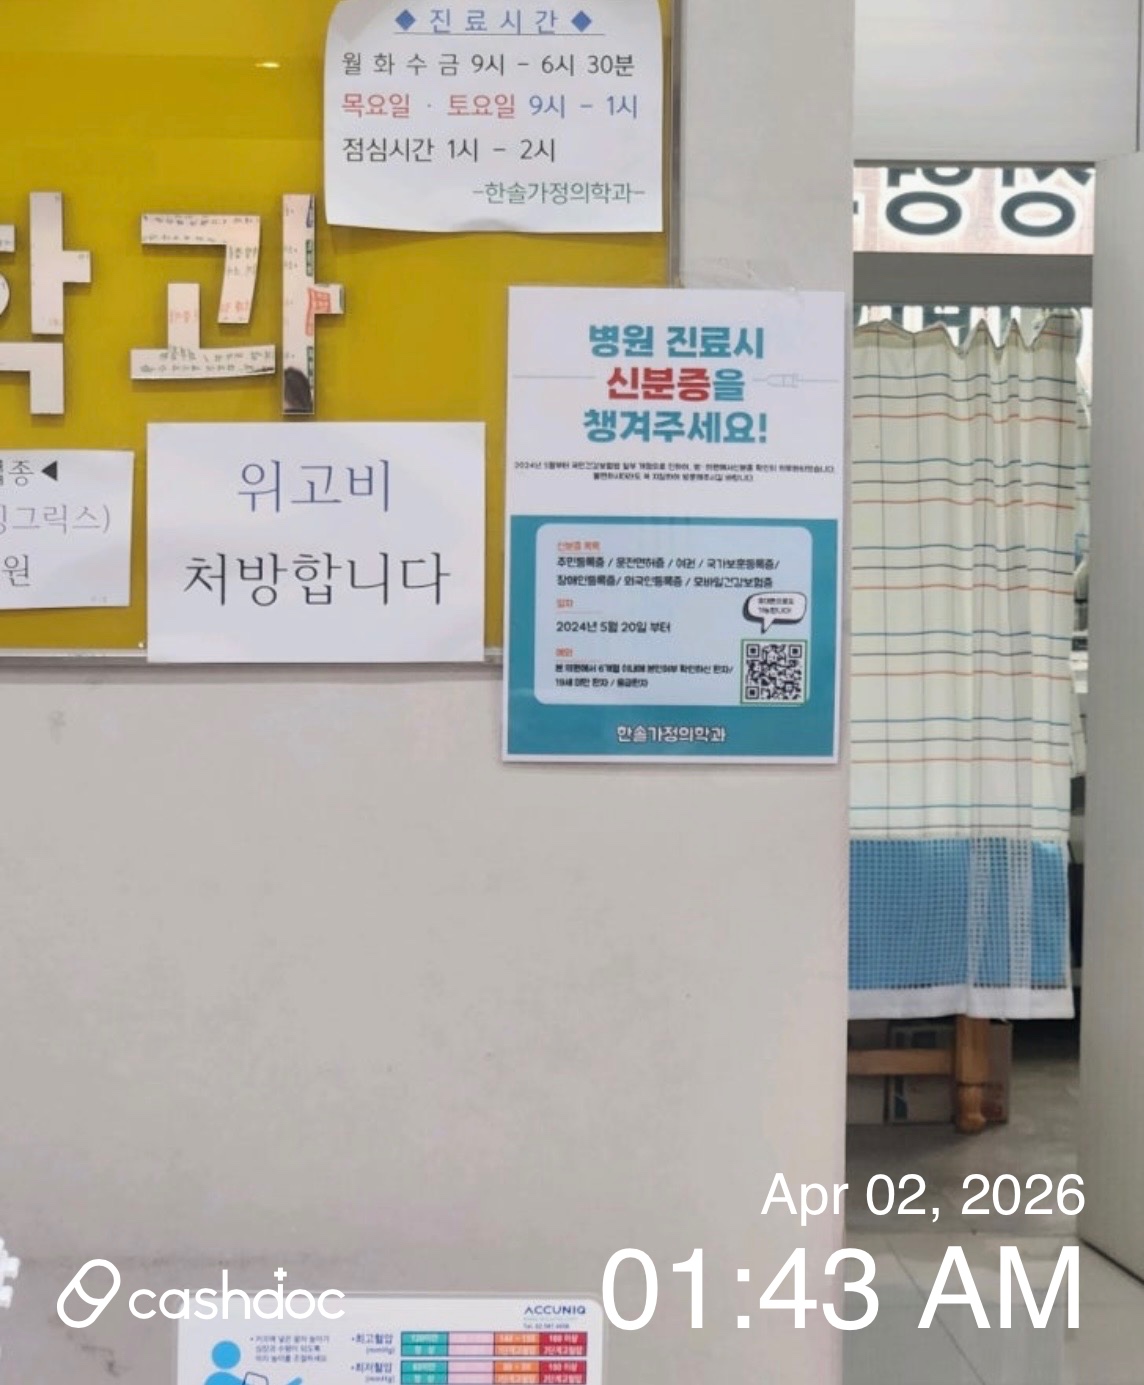

안산시 한솔가정의학과의원, 상담이 너무 짧고 서둘러진 느낌

피부 질환으로 상담을 위해 한솔가정의학과에 문의했는데 전반적으로 아쉬운 점이 있었습니다. 상담 자체는 진행되었지만, 설명이 충분히 이루어지기보다는 비교적 짧게 끝나는 느낌이었고 전…